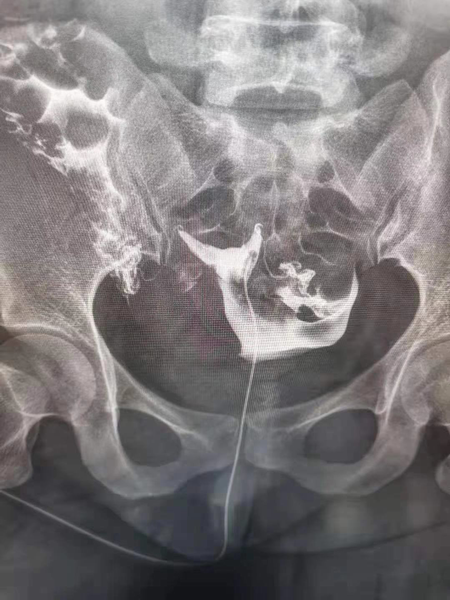

1.造影成像的圖像質量清晰直觀,臨床醫生可以通過讀片來判斷子宮輸卵管腔內的狀態,清晰的圖片對于炎癥、積水等異常診斷更為準確,降低了漏診率和誤診率,對下一步不孕癥的處理方向提高幫助。

2.診斷同起到治療作用,輸卵管內的炎癥碎片、粘液栓、細小的纖維絲均可引起輸卵管的閉塞,并且輸卵管腔內有復雜的皺襞樣結構,造影劑在通過輸卵管腔時,可通過沖刷疏通的作用,改善輸卵管腔內的粘連堵塞,為精子和卵子的運送提供暢通的道路,還可以恢復腔內纖毛的活動,為運送受精卵做好準備。

3.術后妊娠率高,超液態碘化油或碘水除了有沖刷疏通輸卵管的能力外,還具有改善腹腔環境和內膜狀態的效應,術后妊娠率高。